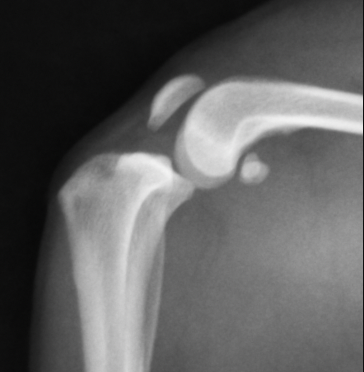

正常な膝関節のレントゲン画像です。大腿骨と脛骨のライン(矢印)がほぼ一致しているのがわかります。

前十字靭帯断裂の膝関節です。ずれているのがおわかりでしょうか?

矢印を入れたものです。正常なものと比較すると一目瞭然でずれているのがわかるかと思います。